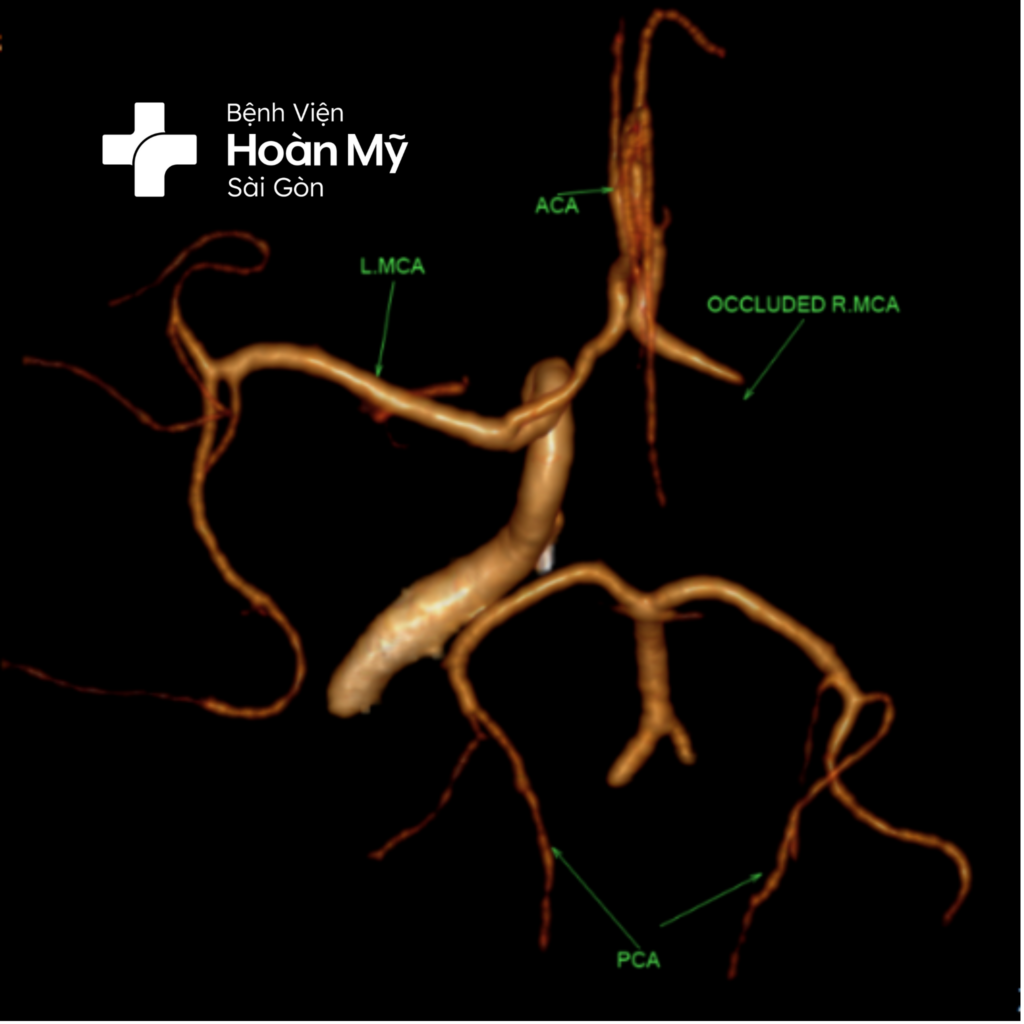

Hình ảnh CT mạch máu não trước can thiệp: Tắc hoàn toàn ĐM cảnh trong và não giữa phải

Hình ảnh ĐM cảnh trong và não giữa phải trước (trái) và sau khi can thiệp (phải)